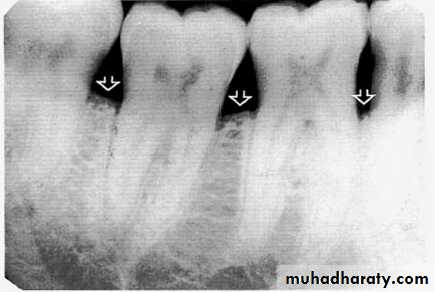

Direction :

Intercrestal bone should be parallel with line dawn from the CEJ of one tooth to that of the contacting tooth.

1. Horizontal bone loss:- When loss occurs on a plane that is parallel with a line drown.

Mild bone loss: crestal changes (The anterior regions show blunting of the alveolar crests and slight loss of alveolar bone height.Posteriorly show loss of the normally sharp angle between the lamina dura and alveolar crest).

Mild bone loss